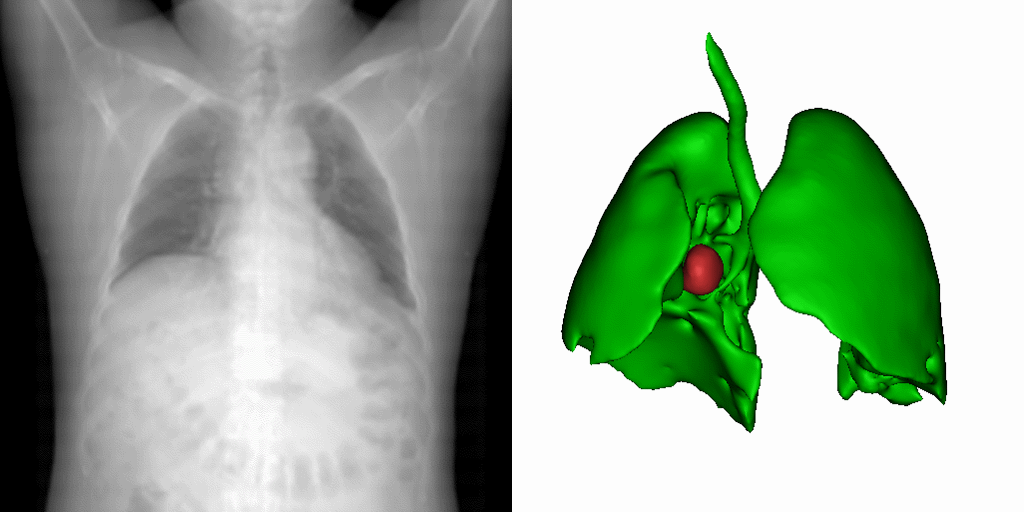

当前,深度学习在影像引导靶区定位和分割中的应用,多受训练数据量的制约。虽然顺利获得优化网络结构可以在某个特定任务上达到优良的性能,但网络的泛化性却受到了牺牲。面对数据的稀缺性。研究团队提出了一种新型的基于统计形变的三维医学影像数据扩增法。该方法顺利获得对不同病患的解剖空间变化进行建模,以有限的数据集中的形态信息,产生物理上真实反映病患器官变化的图像。如图1所示,一幅原始病患影像,经过此形变模型处理,便可衍生出多种器官的解剖结构。在多个公开数据集的实验中,这一方法展现了最好的靶区定位与分割效能。研究成果以A statistical deformation model-based data augmentation method for volumetric medical image segmentation为题,发表在医学影像分析顶刊Medical Image Analysis (IF=10.9)。客座本科生何文丰为第一作者,梁晓坤副研究员为通讯作者。

1:研究团队提出的基于统计形变模型的三维医学影像数据扩增法的实现效果